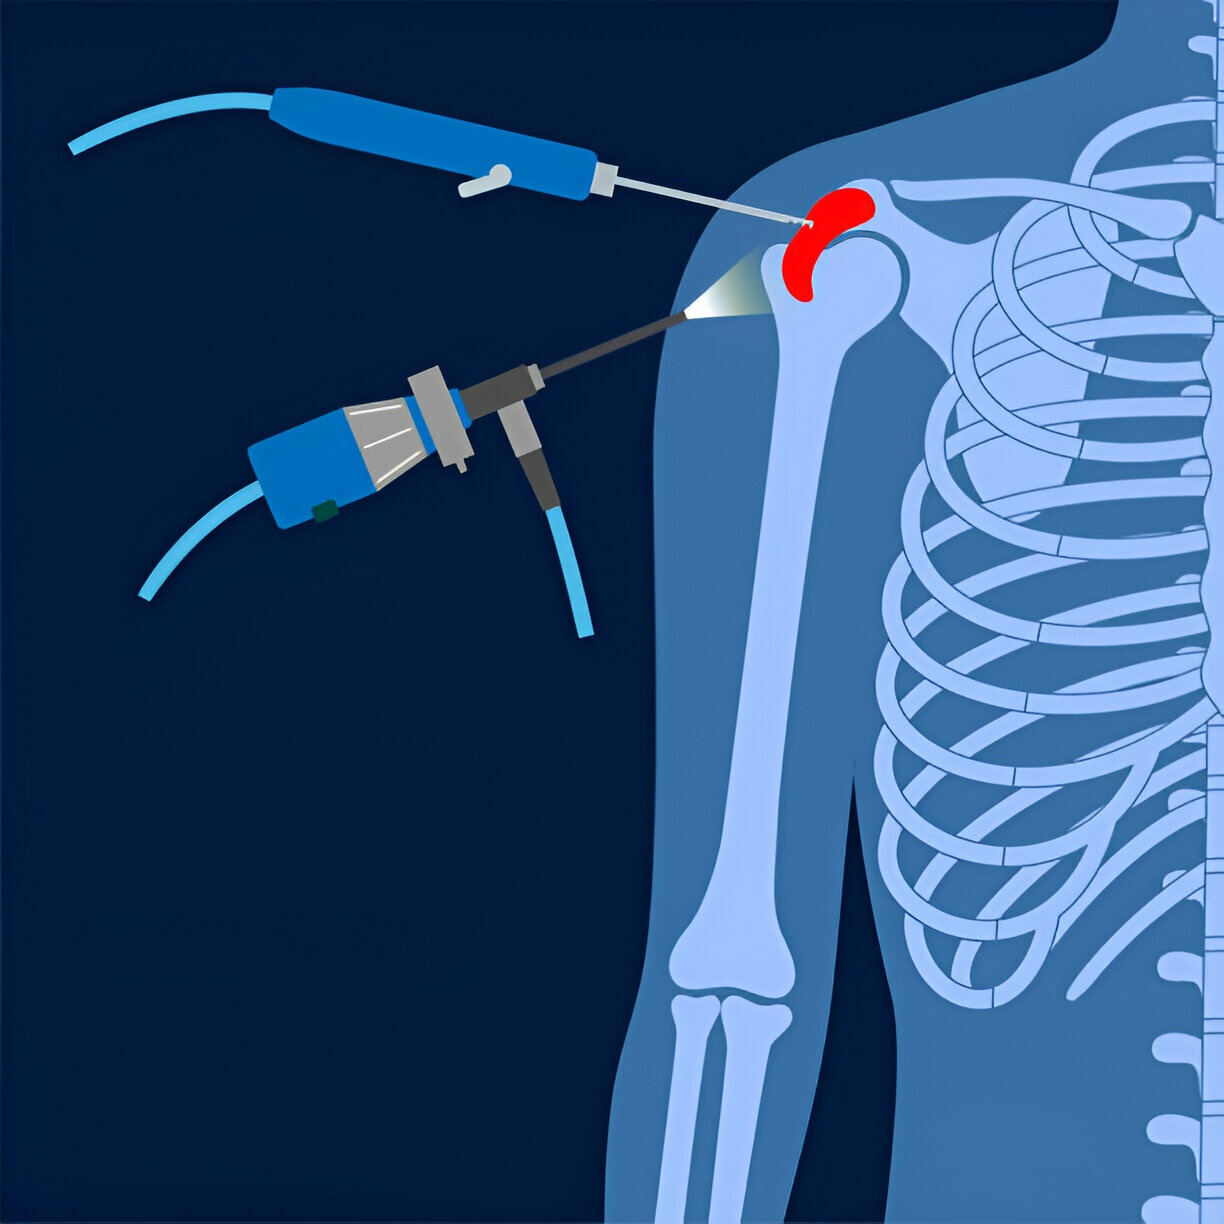

Using orthroscopes, which are small cameras offered in a small incision in the shoulder, a physician can see, diagnose and treat shoulder joints during the shoulder orthroscopy, a minimum invasive surgical process.

Shiner Arthroscopy: If non-surgical treatment options are not effective, then Dr. Ajinkya Bandebuche may recommend arthroscopic shoulder surgery to treat your condition. During the process, he will insert a small camera in your shoulder joint, allowing him to look inside and diagnose the problem. He can then use small surgical devices to repair or remove damaged tissue and restore normal shoulder functions.